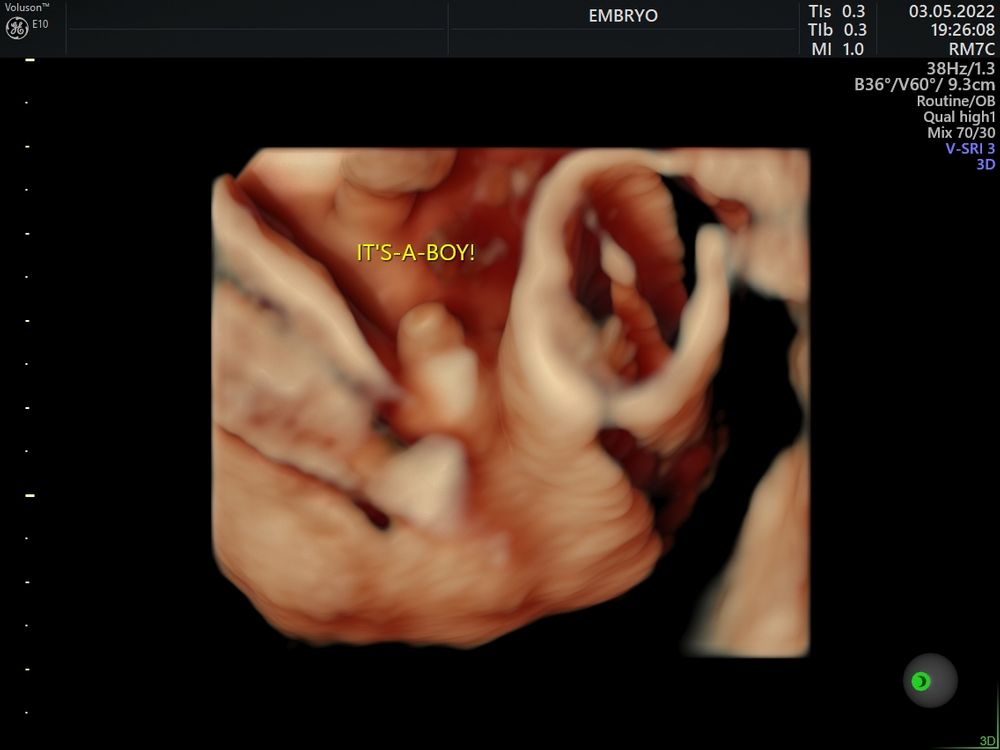

27 недель

27 недель

Ещё в 12 недель определили :)

Ещё в 12 недель определили :)

Разные сроки)

Разные сроки)